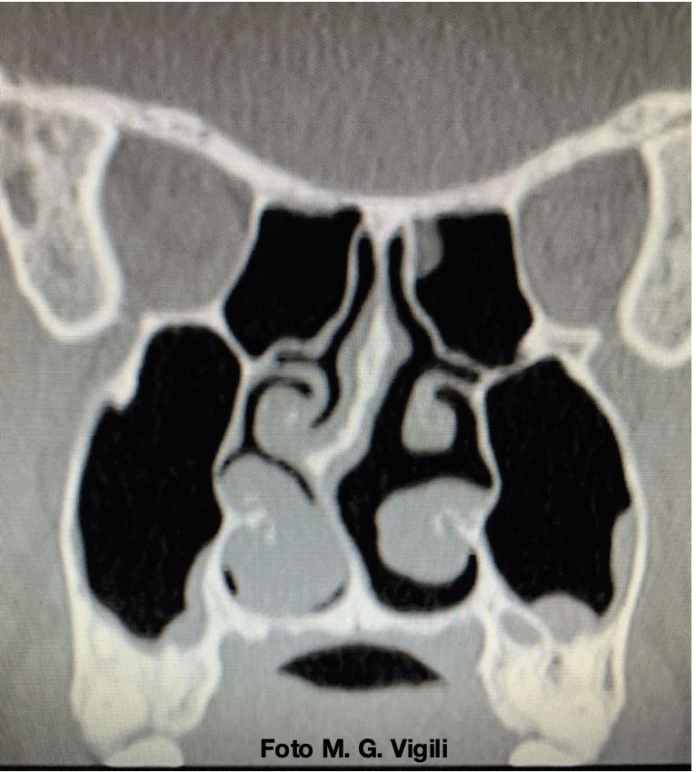

La settoplastica è più efficace della terapia medica nella ostruzione nasale da deviazione settale. Uno studio di metanalisi su 537 lavori che coinvolgevano 721 pazienti ha dimostrato che in pazienti affetti da ostruzione respiratoria con deviazione del setto nasale, l’intervento di settoplastica migliorava significativamente gli score di NOSE e SNOT-22, rispetto a quelli dei pazienti non trattati chirurgicamente.

Le differenze risultavano significative a 6 e 12 mesi mentre a 3 mesi non si evidenziava ancora grande differenza.

L’incidenza di complicanze risultava bassa (0.31% – 4.12%), legata soprattutto a sanguinamento, infezioni e perforazioni settali.

Non avevamo dubbi sulla maggiore efficacia della chirurgia rispetto alle altre terapie nel migliorare la qualità di vita di questi pazienti. Il messaggio importante da recepire è che il risultato ha bisogno di qualche tempo per consolidarsi ed il paziente lo deve sapere per non crearsi false aspettative.